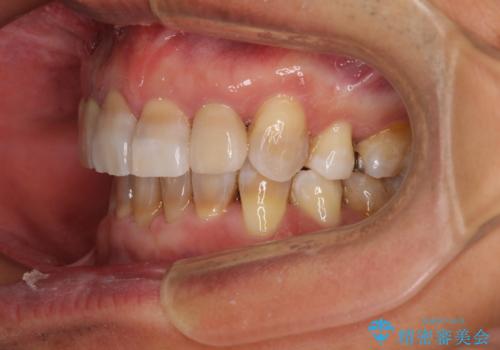

- 骨格的な咬み合わせのズレ、前歯のデコボコとクロスバイトを気にして来院された患者様です。

小臼歯の抜歯する部位を選択したことで、安定した咬み合わせとなりましたが、第二小臼歯を抜歯した部分はスペースを閉じるのに長い期間を要しました。

矮小歯であった上顎前歯2本は、矯正治療後にバランスの取れた大きさのオールセラミッククラウンを装着しました。